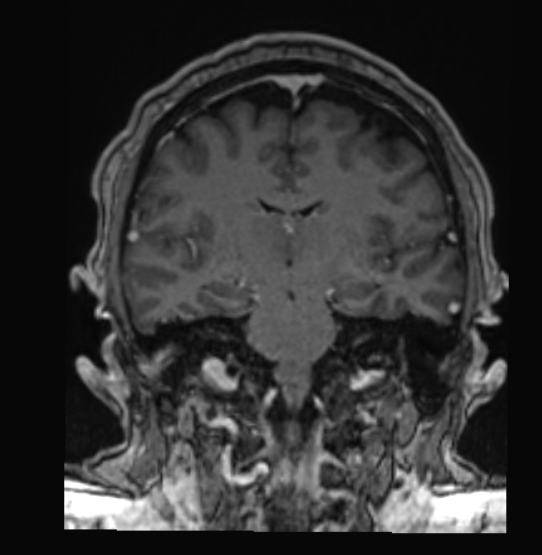

How many business blog posts start with an MRI image of a brain? I mean, it is your biggest asset. It learns, retains, and guides you to your success.

On Monday, I have an urgent appointment with an optometrist. They need to officially diagnose something that was found during imaging, like the one that opens this post today.

My doctor ordered a brain MRI to rule out major disorders. These disorders could cause some of my recent problems. The problems presented as a nerve impingement in my neck, though. That was our suspicion.

I don’t think anyone expected to see signs of Idiopathic Intracranial Hypertension (IIH).

My pituitary gland is being crushed by cerebrospinal fluid (CSF), as observed by a partially “empty” space. My optic nerves (both) are enlarged due to the pressure.